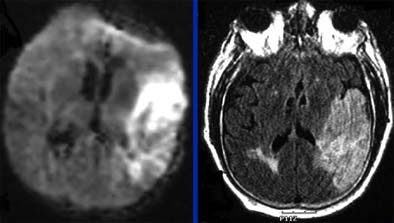

| Follow-up MRI (left, DWI or diffusion-weighted imaging; right, FLAIR technique) in the same elderly male patient shows that area of salvageable penumbra seen in initial CT was not saved, and the entire area has become infarcted. Questions relating to the patient's history of gastrointestinal bleeding led to initial decision to forgo tPA. Diffusion-weighted MRI identifies ischemic but living brain parenchyma at risk for infarction by assesssing the correlation between the diffusion abnormality and the MR perfusion abnormality. Images courtesy of Dr. Jay Cinnamon. |